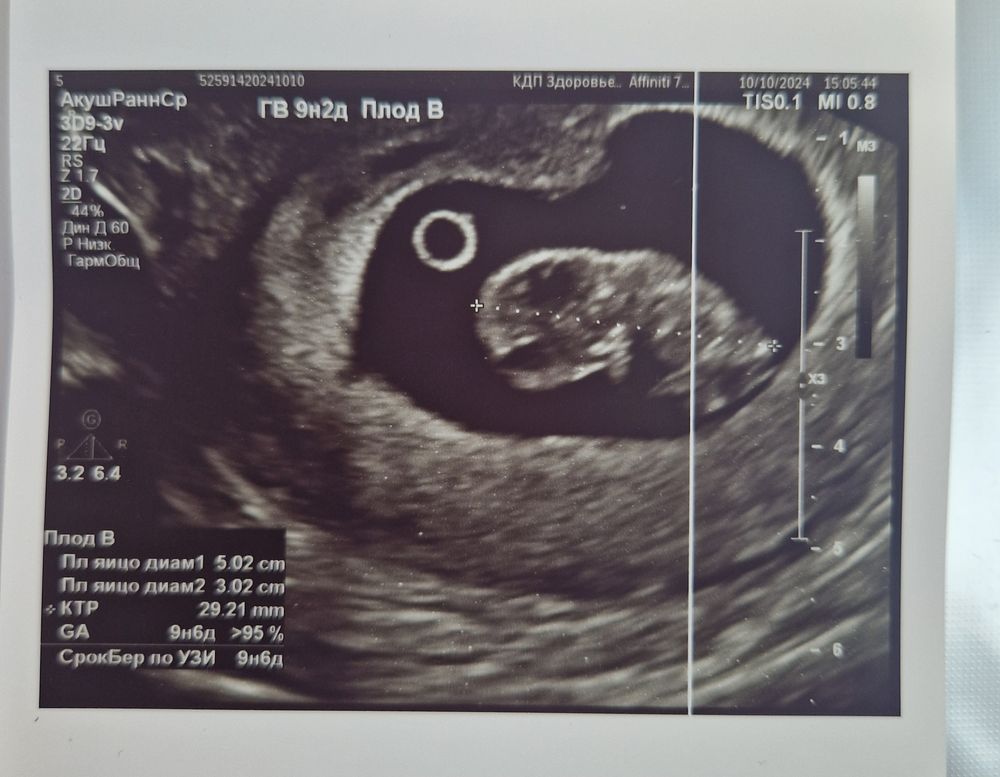

Дарина в Зачатие год Покидайте фото узи в 9 недель 🙏🏻 УЗИ Девочки у кого остались или есть фоточки покидайте пожалуйста! Хочу сходить в 9 неделек на узи, с монитором, хочется узнать как что там примерно видно будет Посмотрите еще 20 записей на эту тему Лучший ответ Елена 9н 2д двойня 02.11.2024 Ответить Отменить Ответить Таня Орозова 01.11.2024 Ответить Екатерина 01.11.2024 Ответить Екатерина Екатерина, чуть больше, 9,5 01.11.2024 Ответить Евгения 9+3 недели 01.11.2024 Ответить ЛисАлис 01.11.2024 Ответить Екатерина 01.11.2024 Ответить Екатерина Екатерина, 9 недель ровно, первое УЗИ 01.11.2024 Ответить Екатерина Екатерина, ножки попка к верху 😄 01.11.2024 Ответить Дарья 01.11.2024 Ответить Евгения Дарья , а вам делали трансвагинально или абдоминально? 01.11.2024 Ответить Дарья Евгения, трансвагинально . А вот 10 недель узи) 01.11.2024 Ответить Евгения Дарья , ух ты) а мне абдоминально делали😁 как в этот раз будут не знаю, пойду в другое место 01.11.2024 Ответить Евгения 01.11.2024 Ответить Мира В интернете нашла)) 01.11.2024 Ответить Девочки подскажите !! Пост нытья Чаты Беременных Выберите чат: Январята-2026 Февралята-2026 Мартята-2026 Апрелята-2026 Майчата-2026 Июнята-2026 Июлята-2026 Августята-2026